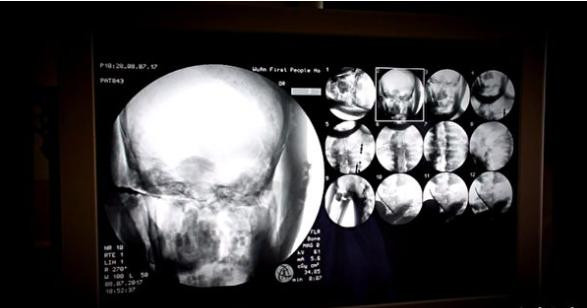

Khi chụp X-quang, các chuyên gia phát hiện xác ướp nhà sư hơn 1.000 tuổi còn nguyên bộ xương và sọ não. Điều này vô cùng hiếm có và khó tin.

Cụ thể, các chuyên gia tiến hành chụp X-quang xác ướp nhà sư Từ Hiền. Nhờ vậy, họ phát hiện thi hài nhà sư Từ Hiền vẫn còn đầy đủ xương cũng như sọ não.

Theo các chuyên gia, xương hàm trên, hàm dưới, xương sườn, cột sống và tất cả khớp của nhà sư Từ Hiền đều hoàn chỉnh. Điều này khiến giới khoa học cảm thấy bất ngờ và khó tin.